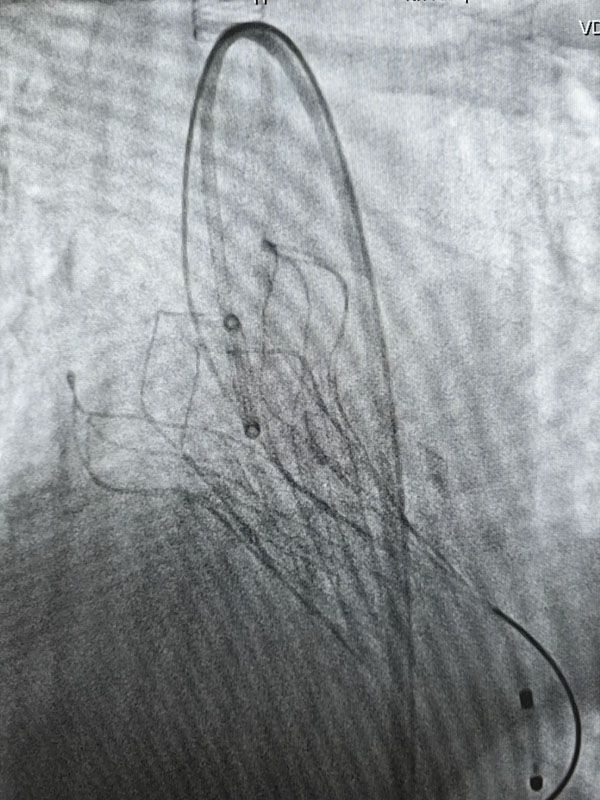

經(jīng)過充分的術前準備,兩臺手術由心血管外科趙永波副主任主刀,趙偉超主治醫(yī)師、侯五輝主治醫(yī)師密切配合,選擇經(jīng)皮股動脈穿刺,預埋縫合器,術中反復造影,準確定位釋放瓣膜,術后造影及超聲提示人工瓣膜開啟功能良好。為確保術中安全,體外循環(huán)小組全程保駕護航。患者生命體征平穩(wěn),術后一日均轉出監(jiān)護室。